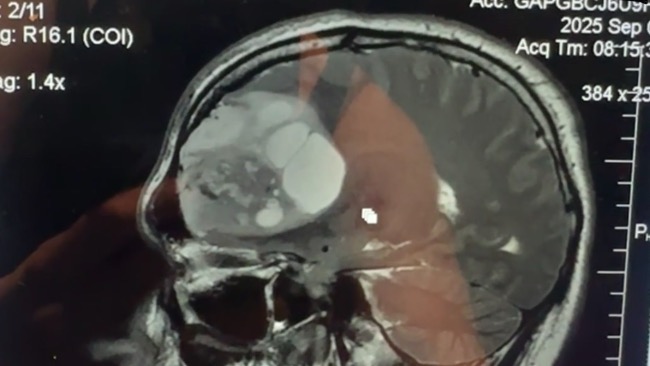

Mój syn, młody mężczyzna pełen marzeń i pasji — zwłaszcza do motocykli — pod koniec sierpnia 2025 roku zaczął odczuwać dziwne objawy: mrowienie twarzy i problemy ze wzrokiem. Myśleliśmy, że to zwykły problem z zatrzymaną ósemka naciskająca na nerw. Tymczasem 5 września dowiedzieliśmy się, że ma guza mózgu o wielkości 70x56x68 mm. Trzy tygodnie później, 3 października, usłyszeliśmy diagnozę, która złamała nam serca — glejak IV stopnia.

Przeszedł ciężką operację całkowitej resekcji guza, po której niestety wystąpiły powikłania. Początkowo doszło do zakażenia, które wymagało kraniektomi czaszki i wyczyszczenia stanu zapalnego, który tam powstał. Później pojawiły się problemy z płynem mózgowo-rdzeniowym, a podczas bardzo bolesnego zabiegu założono mu dren do kręgosłupa, który niestety został umieszczony nieprawidłowo i dzień później musiał przejść kolejny zabieg, by dren założyć we właściwe miejsce. Te komplikacje dodatkowo osłabiły jego organizm i utrudniły rekonwalescencję.